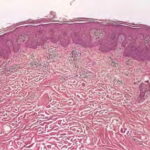

PATHOLOGY

Pathologic findings in pityriasis rubra pilaris vary according to the duration of the disease. The findings are most likely to be diagnostic in the acute phase, when hyperkeratosis, acanthosis with broad short rete ridges, and alternating orthokeratosis and parakeratosis oriented in both horizontal and vertical directions can be observed (see Pityriasis Rubra Pilaris At a Glance). Usually, there is a sparse superficial, perivascular lymphocytic infiltrate in the underlying dermis. Keratinous plugs of the follicular infundibula as well as perifollicular areas of parakeratosis may also be present. A prominent granular layer and dilated, but not tortuous, capillaries are features that help to distinguish pityriasis rubra pilaris from psoriasis, the most important differential diagnosis.